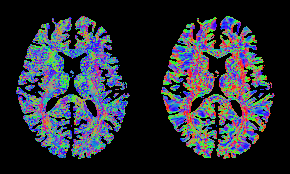

Figure 2. Color-coded orientation of the spatial gradient of the image for the HCP subject, estimated: from the diffusion signal using the proposed approach (left) and from the b=0 image via the finite-element approach (right). Consistent fiber orientations are observed mostly in single-fiber regions, which may be due to the limitations of the DTI model at regions with fiber crossing.